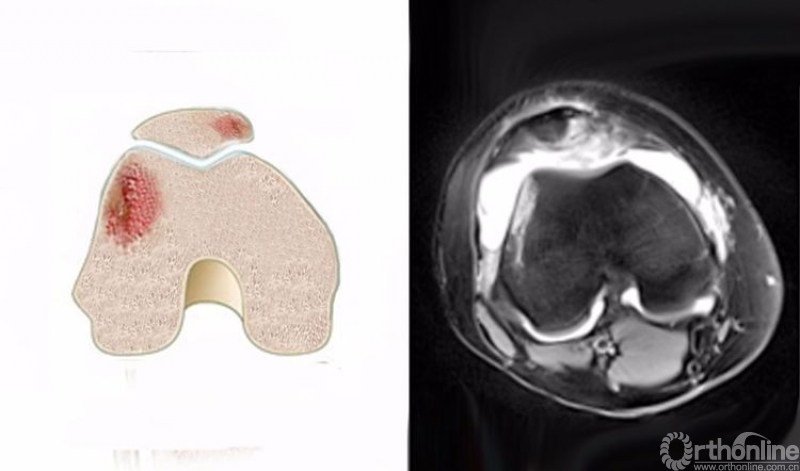

5.髌骨脱位(patellar dislocation)

髌骨脱位是一种常见的损伤,其损伤是短暂性的,病人不一定意识到,而在体检时由于肿胀和疼痛而影响检查,因此有50%-70%的患者在初次就诊时不能获得诊断。

髌骨脱位是髌骨内侧与股骨外髁外侧壁发生撞击,在MRI上主要表现为髌骨内侧及股骨外髁外侧壁的骨髓水肿,T2WI及STIR像呈高信号改变。可合并内侧髌股副韧带撕裂、髌骨及其股骨外髁的骨软骨损伤。